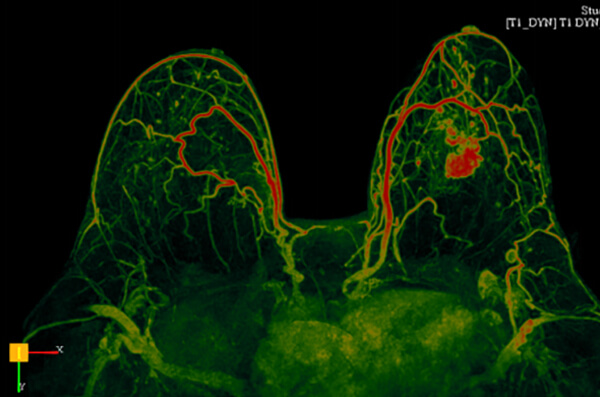

Οι ειδικές τεχνικές μαγνητικής τομογραφίας παίζουν σημαντικό ρόλο στην ανίχνευση και την αξιολόγηση της έκτασης του καρκίνου του μαστού. Με τη χρήση τους, η διαγνωστική ακρίβεια κατά την ταυτοποίηση και τον χαρακτηρισμό μιας βλάβης αυξάνεται σημαντικά, συμβάλλοντας έτσι στην επιλογή της κατάλληλης θεραπείας και τη σωστή παρακολούθηση του θεραπευτικού αποτελέσματος.

- Έχει πολύ υψηλή ευαισθησία στην ανίχνευση του κλινικά σημαντικού καρκίνου (διηθητικό καρκίνο και high grade in situ) και υπερτερεί της μαστογραφίας στην απεικόνιση των πυκνών μαστών, στις οποίες ανιχνεύει έως και διπλάσιο αριθμό καρκίνων

- Δυναμική αγγειογραφία (4D time resolved TWIST)

- Επεξεργασία των δεδομένων σε σύστημα CAD